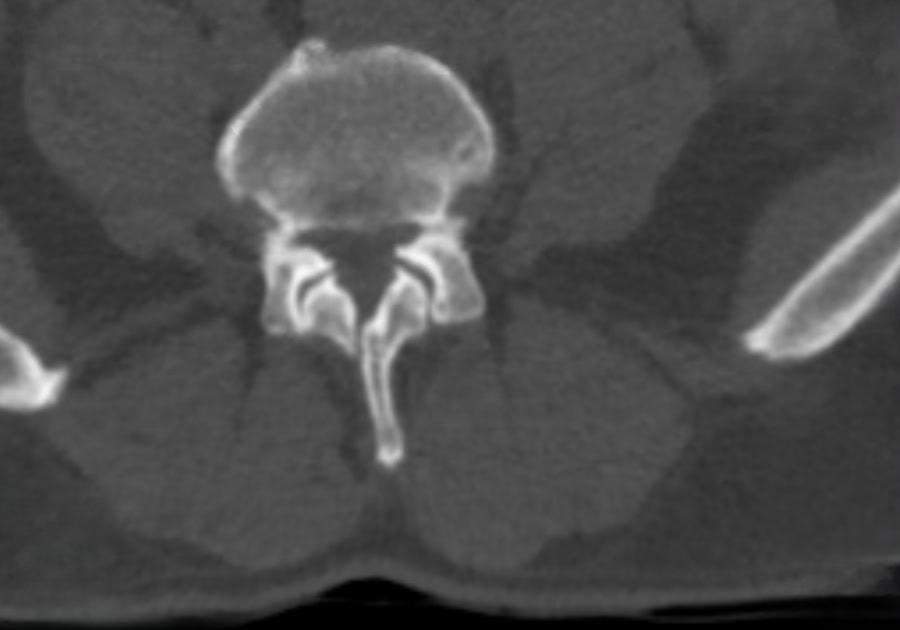

Preop.

2-Year Postop

2-year Postop.